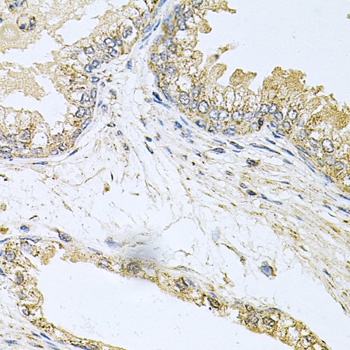

Immunohistochemistry of paraffin-embedded human stomach using BCR at dilution of 1:100 (40x lens).

Immunohistochemistry of paraffin-embedded human prostate using BCR at dilution of 1:100 (40x lens).